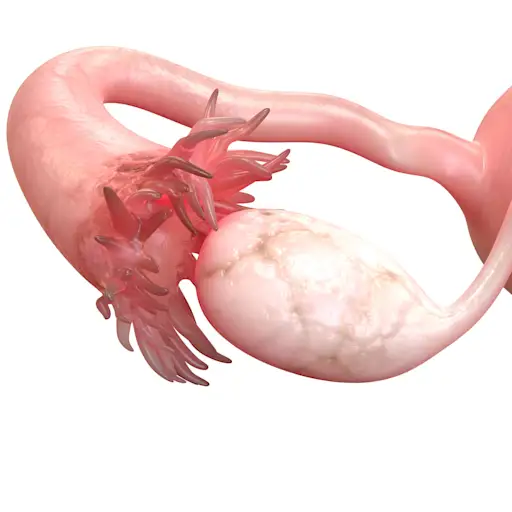

输卵管

iStock

壁内肌瘤导致阻塞

塞加尔斯博士说,子宫壁可能会影响生育能力的另一种邪恶方式是阻止输卵管,但您可能没有意识到这一点。他说,如果有完全的障碍,那么怀孕的机会降至零。塞加尔斯博士说:“它们可以阻止一个或两个试管……这不一定可以在超声波上检测到。”要查看您的试管是否被肌瘤阻塞,您需要盐水超声图或滞后图(HSG),该过程使用放射性染料突出显示障碍物并检查正常流向子宫。